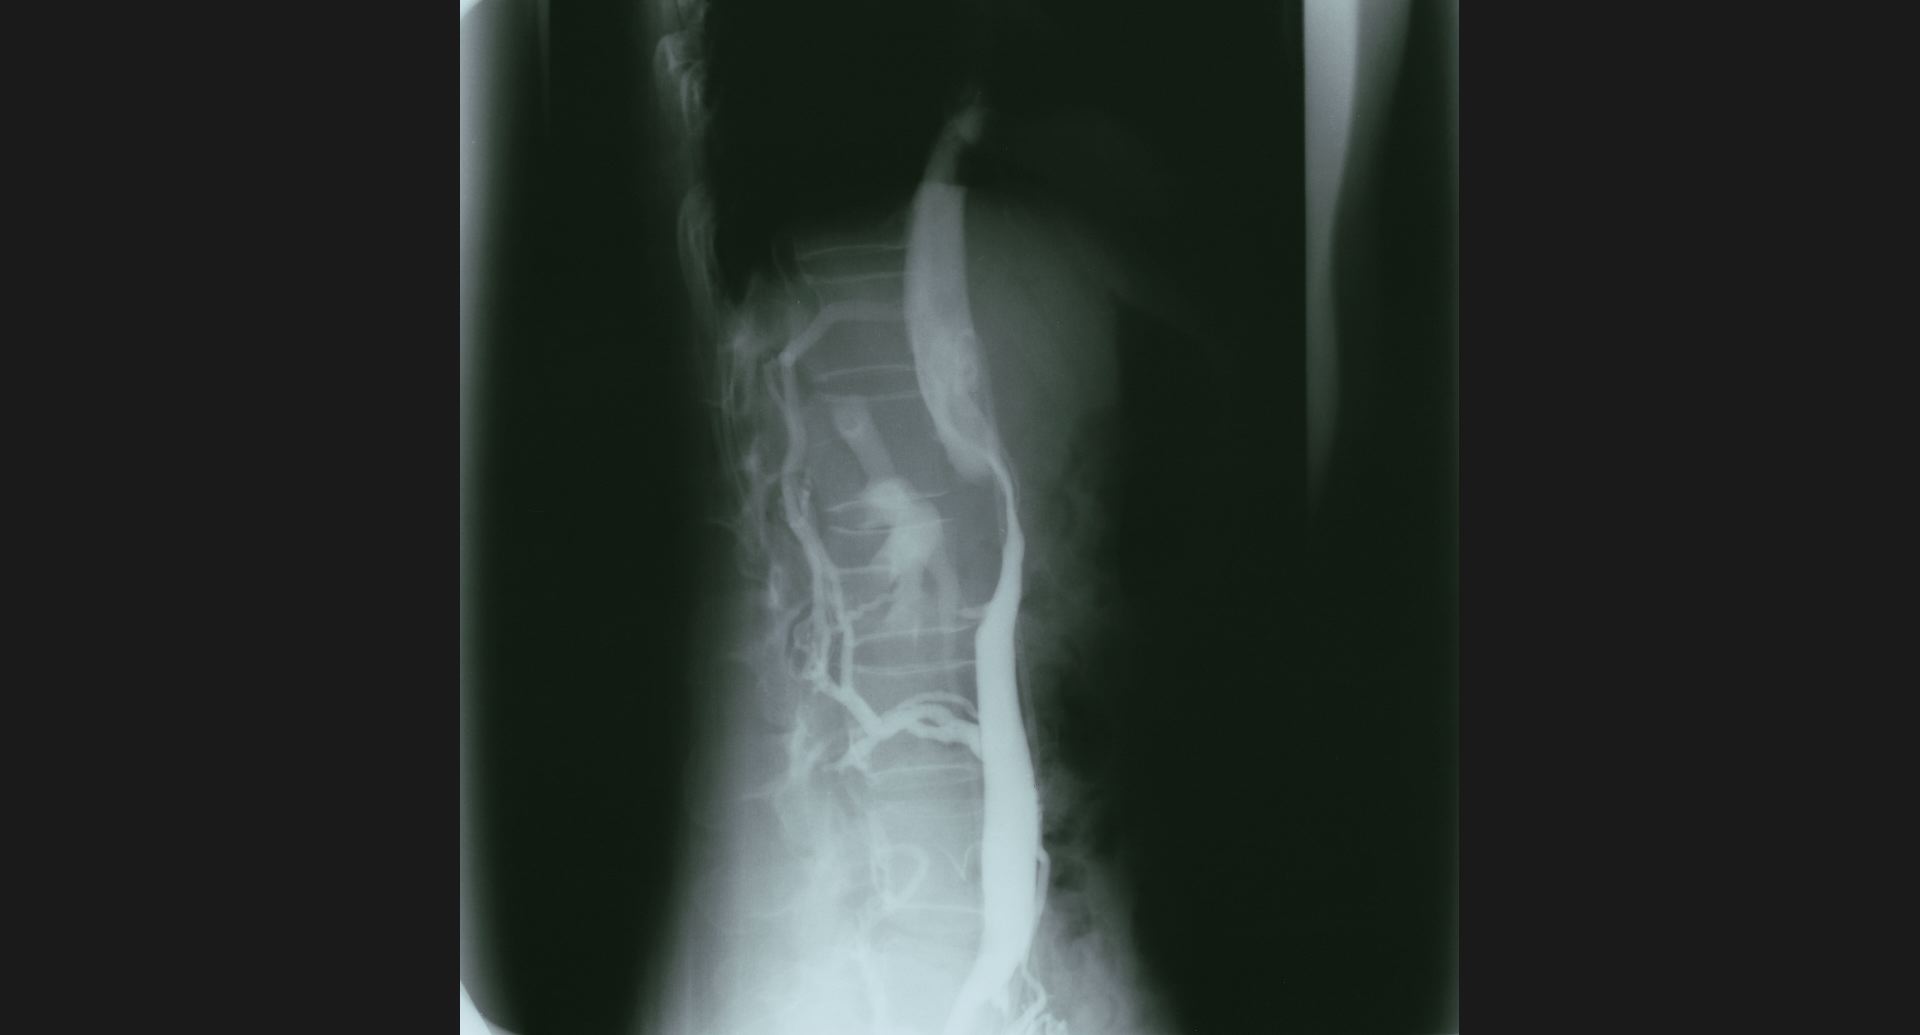

fig.11(59KB) :IVC stenosis (cavography), lateral view

collateral vein。狭窄。